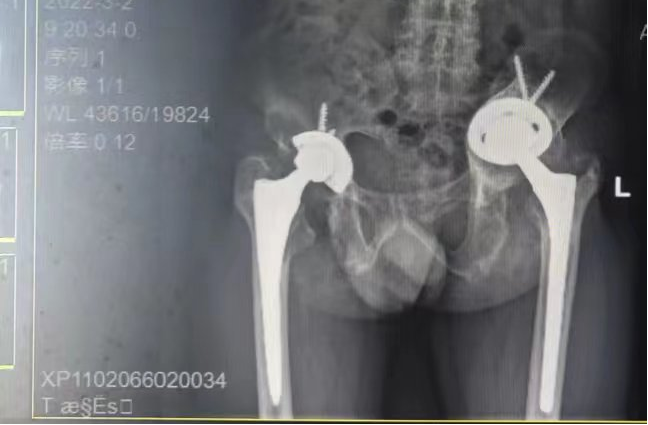

翻修术后

9月,患者入院后经我院骨科团队充分评估及讨论,完善相关术前检查、详细制订手术方案及术前准备,张勇华副院长与骨科手术团队为患者顺利完成人工髋关节翻修术。术后,经过医护人员的精心治疗和康复护理指导,患者住院期间已在助行器辅助下站立、行走,伤口愈合出院。